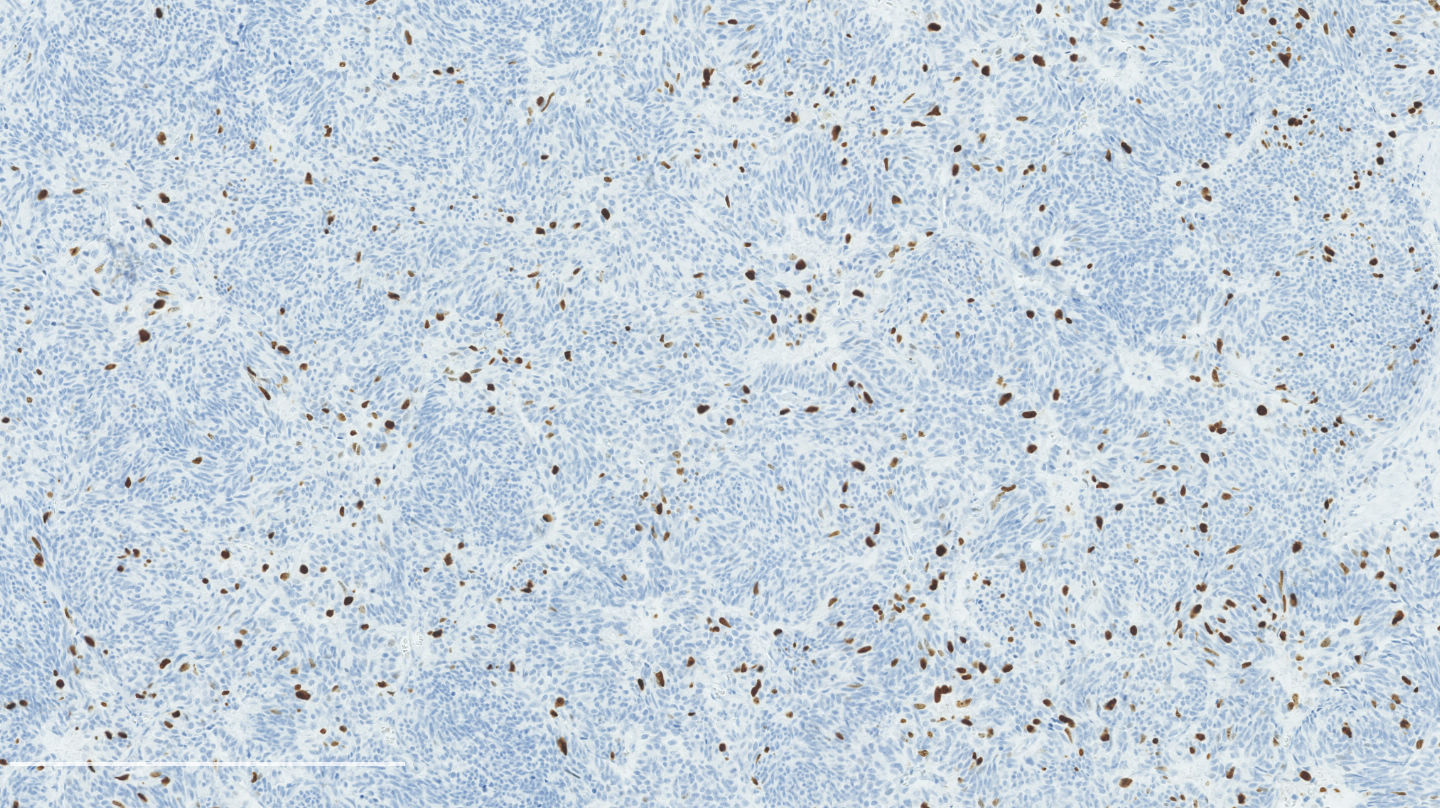

Microscopic (histologic) description

- Diagnostic criteria:

- Neuroendocrine morphology with 2 - 10 mitoses per 2 mm² or presence of necrosis

- Necrosis can be in large zones but is usually punctate

- Mitotic rate should be counted in the area with the highest proliferation rate (hot spot)

- If mitotic rate is near cutoffs, assessment should be made on three sets of 2 mm² and their mean should count as the final mitotic rate

- Neuroendocrine morphology with 2 - 10 mitoses per 2 mm² or presence of necrosis

- Neuroendocrine histologic patterns similar to typical carcinoids: organoid, trabecular, rosette formation, papillary, pseudoglandular, follicular

- Tumor cells are as typical carcinoid: uniform with a polygonal shape, round to oval nuclei with salt and pepper chromatin and inconspicuous nucleoli, along with moderate to abundant eosinophilic cytoplasm

- Greater pleomorphism than for typical carcinoid is common (Arch Pathol Lab Med 2010;134:1628)

- Spindle cells and clear cell features can be seen

- Stroma is fine and highly vascularized; hyalinization, cartilage or bone formation are possible

Microscopic (histologic) images

Contributed by Philippe Joubert, M.D., Ph.D.

Positive stains

- Chromogranin, synaptophysin, CD56: diffusely and strongly positive; can be negative in a small number of atypical carcinoids (Hum Pathol 2000;31:1255)

- Ki67: should not be used as a diagnostic criterion (J Thorac Oncol 2019;14:377)

- Mostly useful to differentiate lung carcinoids from high grade neuroendocrine carcinomas, in particular in small biopsies or cytology samples (Arch Pathol Lab Med 2018;142:947, J Thorac Oncol 2014;9:273)

- Usually < 20% but a > 30% cutoff has been proposed (Virchows Arch 2017;470:153, J Thorac Oncol 2014;9:273)

- Reported to be higher than typical carcinoid (2 - 5% versus 9 - 18%) but not proven to be a reliable marker